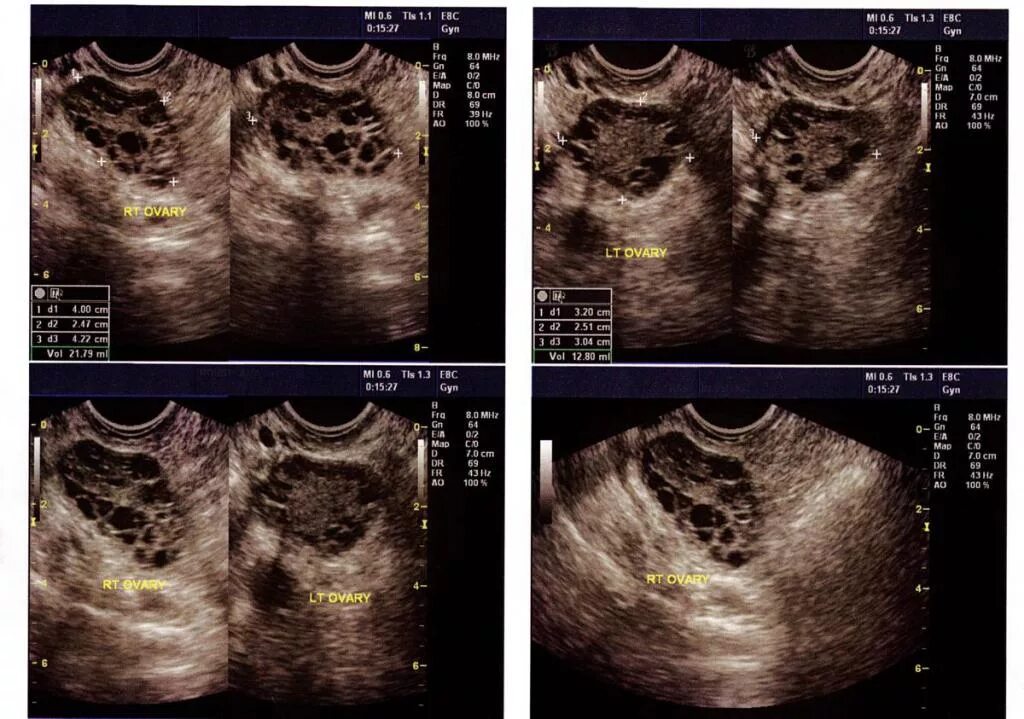

Рак яичников